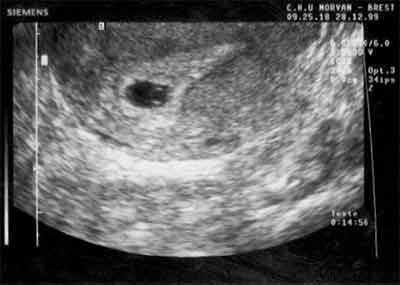

b HCG 3640